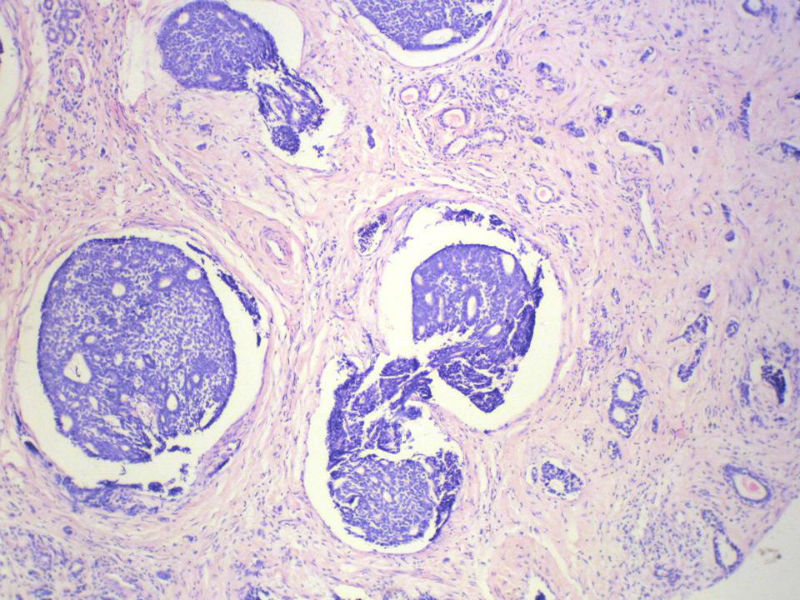

男,76岁,鼻塞两个月,CT提示左上颌窦占位,局部骨质破坏,口腔硬腭下降,局部活检。

腺样囊性癌,图像很典型的